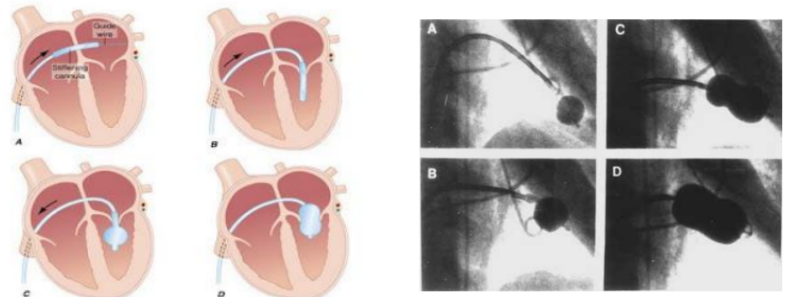

- Nong van hai lá bằng bóng:

- Đưa bóng nong (đã được làm căng) vào nhĩ trái dựa trên wire vòng,

- Dùng que lái bóng đưa bóng nong qua lỗ van hai lá

- Bơm bóng nong từng bước để tách mép vao hai lá, đánh giá áp lực nhĩ trái, khả năng bị hở van hai lá tăng... để quyết định tăng cỡ bóng tối ưu

Hình 15.1 : Quy trình nong van hai lá bằng bóng Inoue